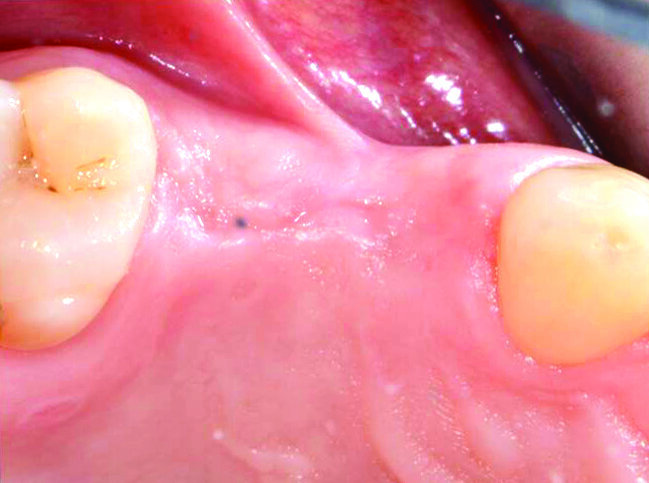

Paziente donna di 45 anni, non fumatrice, presenta alla nostra attenzione un’edentulia parziale superiore, in seguito all’estrazione di 2 elementi avvenuta 8 settimane prima (Fig. 1). L’anamnesi medica per patologie sistemiche risulta negativa. Gli indici di placca (FMPS) e sanguinamento (FMBS) presentano valori rispettivi di 16 e 12. L’esame intraorale rivela una sella edentula estesa per circa 18 mm in senso mesio-distale, dall’elemento 13 al 16 (Figg. 2, 3).

Fig. 3_Visione occlusale della sella edentula: si può apprezzare l’inserzione bassa del frenulo vestibolare laterale.